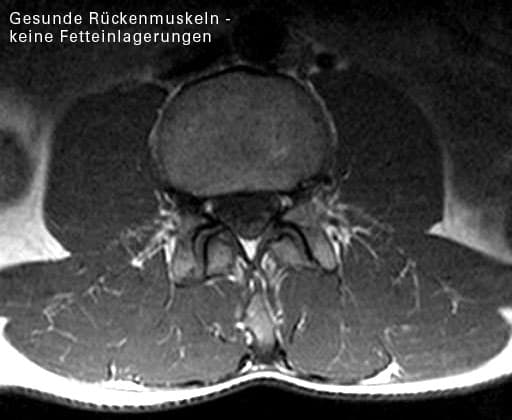

Abbildung degenerierter Rückenmuskel

Ein Muskelschwund am Oberschenkel ist leicht erkennbar. Man hat den Vergleich zur Gegenseite. An der Wirbelsäule hat man keinen Vergleich. Den Muskelschwund spürt man durch Kreuzschmerzen. Man kann ihn allerdings im Kernspin sehen.

Ohne Beeinflußbarkeit durch den Willen scheint es noch eine "reflektorische" Muskelhemmung zu geben. Oft fällt in Kernspinaufnahmen auf, daß eine isolierte fettige Degeneration der Rückenmuskulatur vorliegt genau auf der Höhe und der Seite eines Bandscheibenvorfalles.